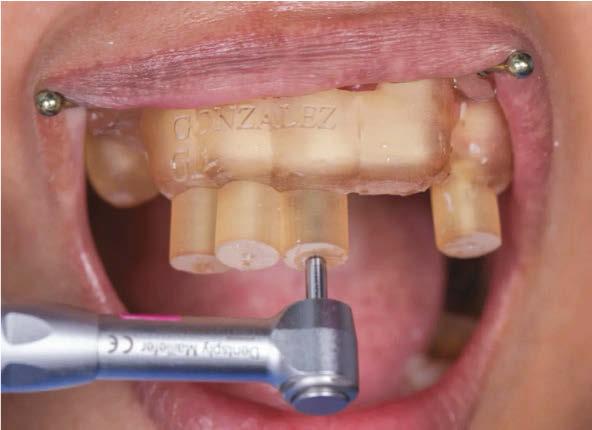

How has the new X-Smart Pro+ streamlined your workflow and impacted your day?

The combination of the apex locator and motor into one single piece of equipment really streamlines the work setup and leaves less clutter on the work surface. The X-Smart Pro+ allows us to work efficiently and effectively to ensure the canals are instrumented to length. I appreciate not having to stop and switch back to the apex locator to confirm working lengths. For appointments where every second counts, this combination method is a game changer. The added light source is especially helpful when accessing through small spaces, crowns, and heavily restored teeth. The file library is also advantageous to my daily workflow. Like most endodontists, I tend to hybridize the file systems to match the anatomy of the case in front of me. I can custom set specific file sequences among the systems to create the instrumentation pattern that best matches my needs.

Left: XSmart ProPlus. Right: Reciproc Blue file

I recently switched to the X-Smart® Pro+ in some ops with the combined apex locator. Other ops still have the ProMark motor, and it really just comes down to provider preference.

I use a variety of Dentsply files, and it all depends on the individual tooth. On any given day, I will likely have used ProTaper Ultimate™, ProTaper Gold®, Pro Taper® Universal, WaveOne® Gold, and now Reciproc™ Blue. I often customize my protocol and sequence based on the anatomy from the cone beam scan.